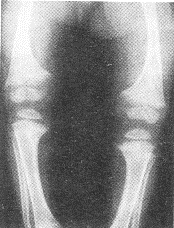

患儿女性,2岁,睡眠差、哭闹、易出汗;双腿呈"O"形。X线平片如图所示。

正确答案:1.D;2.ABDEF;3.ABCDEF 解题思路:长骨的骨干可因骨膜下骨样组织形成而变粗,且边缘模糊。